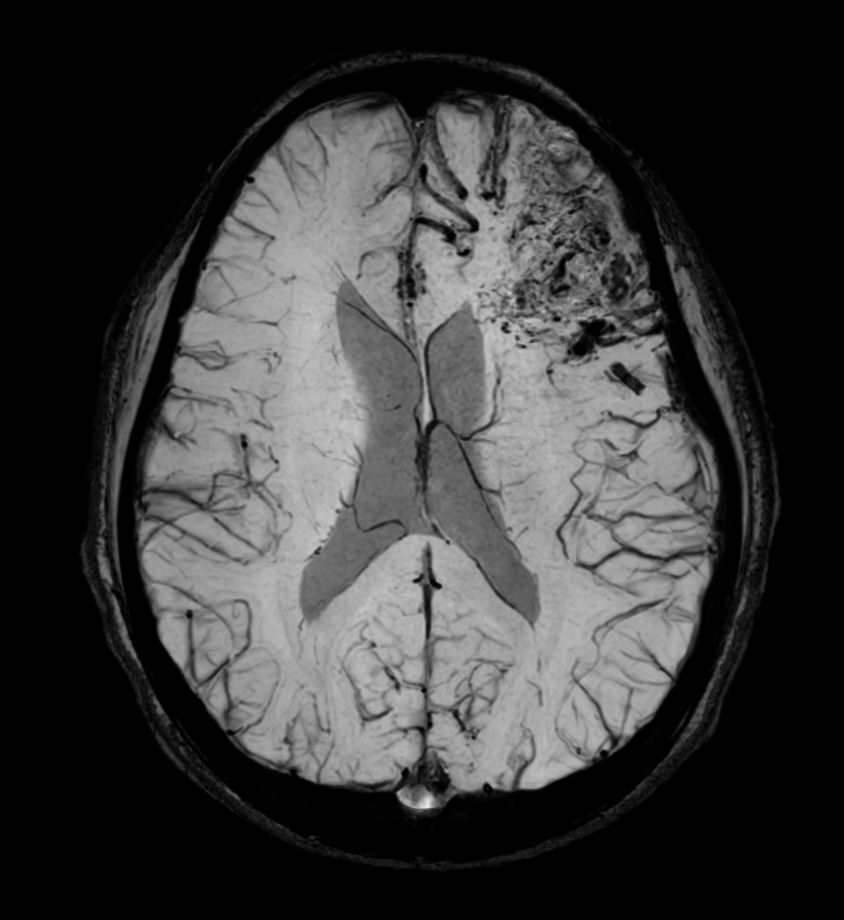

Pediatric brain with AVM

Pediatric patient with frontal brain AVM. MultiVane XD is used to achieve high resolution diagnostic images, even in the case of severe patient motion. SWIp sequence is added to acquire exquisite susceptibility contrast. The 3D sequences with isotropic voxel size enable reformats in any plane without loss of resolution. And 4D-TRAK XD, a fast, dynamic contrast-enhanced MR Angiography method allows to achieve high spatial and temporal resolution simultaneously. Integration of Compressed SENSE acceleration technique enables speeding up of the entire exam.

3D T1w TFE - Axial reformatCompressed SENSE